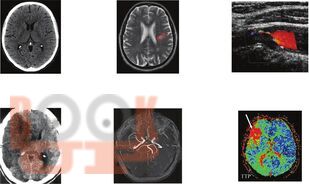

В учебнике представлены основные сведения по частной клинической неврологии, входящие в программу изучения дисциплины в медицинских ВУЗах. Изложена базовая информация и новейшие научные сведения об этиологии, патогенезе, клинике, диагностике и лечении наиболее значимых и распространенных заболеваний нервной системы в удобном для восприятия формате — в виде таблиц и блок-схем.

Учебник предназначен для студентов медицинских ВУЗов, обучающихся по специальности 31.05.01 «Лечебное дело» и 31.05.02 «Педиатрия», будет полезен для ординаторов, аспирантов, изучающих неврологию и нейрохирургию, врачей неврологов, терапевтов, педиатров, врачей общей практики и др.